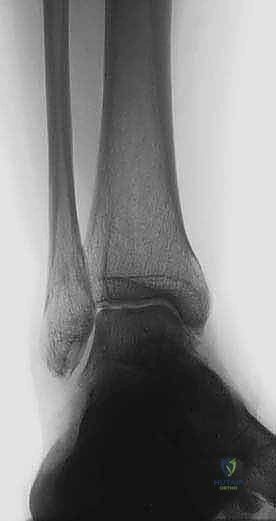

2. التصوير بالأشعة السينية بوضعية الوقوف (Weight-bearing X-rays)

هذا هو حجر الأساس في التشخيص. الأشعة العادية والمريض مستلقٍ لا تظهر الحجم الحقيقي للتشوه. يطلب الدكتور هطيف صوراً خاصة والمريض يحمل وزنه كاملاً على قدميه.

* المنظر الأمامي الخلفي (AP View): لتقييم المسافة المفصلية وتحديد زاوية سطح الساق (Tibial Anterior Surface Angle - TAS).

* منظر سالتزمان (Saltzman View): وهو منظر إشعاعي متخصص جداً لتقييم محاذاة الكعب الخلفي بالنسبة لمحور الساق، وهو أمر حاسم في التخطيط الجراحي.